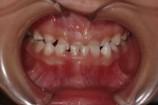

「叢生」は、一般的に「乱ぐい歯(らんぐいば)」「八重歯(やえば)」「ガタガタの歯並び」などと呼ばれる状態で、日本人に非常によく見られる不正咬合(ふせいこうごう:良くない噛み合わせ)です。

<叢生の状態>

顎(あご)の骨の大きさに対して、歯のサイズが大きすぎたり、歯が並ぶスペースが不足していたりするために、歯がデコボコに重なり合って生えている状態を指します。